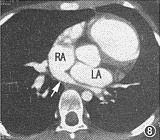

图1~6 为同一病例,部分型肺静脉异位连接(心脏型)。图1示右上肺静脉(短箭头)引流入右心房(RA),左上肺静脉(长箭头)引流入左心房(LA),房间隔缺损巨大。图2示两下肺静脉(箭头)分别引流入左右心房。RV:右心室;LV左心室。图3示下腔静脉肝段缺如:肝脏水平未见下腔静脉显影,半奇静脉粗大(箭头)。图4为表面阴影显示法三维重建,示右侧上下肺静脉(白箭头)均引流入右心房,左侧上下肺静脉(黑箭头)均引流入左心房。SVC:上腔静脉。图5为导管自下腔静脉经奇静脉入右心房经右心室至右肺动脉造影:右肺静脉(黑箭头)引流入右心房(白箭头)。图6为左肺动脉造影,示左肺静脉(白箭头)引流入左心房(白三角箭头),对比剂经房间隔缺损(黑箭头)分流入右心房